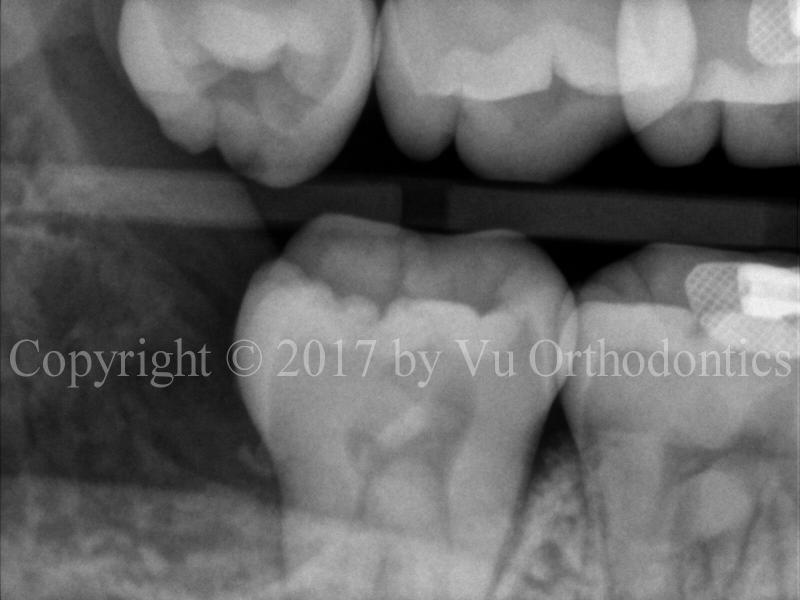

Figure 4 shows an example of the impacted lower right wisdom tooth (#32). The tooth is horizontally impacted and almost completely bony. The extraction was done without the socket graft. The result is, more than likely, that there will be a bony defect on the distal side of the lower right second molar (tooth #31).

(a)

(b)

(c)

Fig. 4 Bony defect on the distal side of Tooth #31, after the wisdom tooth #32 is extracted without socket graft: (a) before extraction, (b) BW radiograph after extraction, (c) PA radiograph after extraction